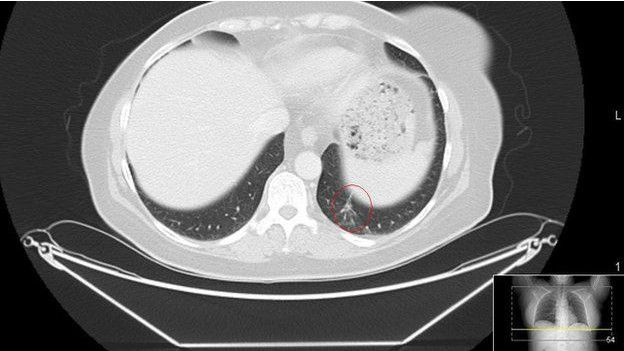

Томограф показав, що після імунотерапії розміри пухлини сильно зменшилися